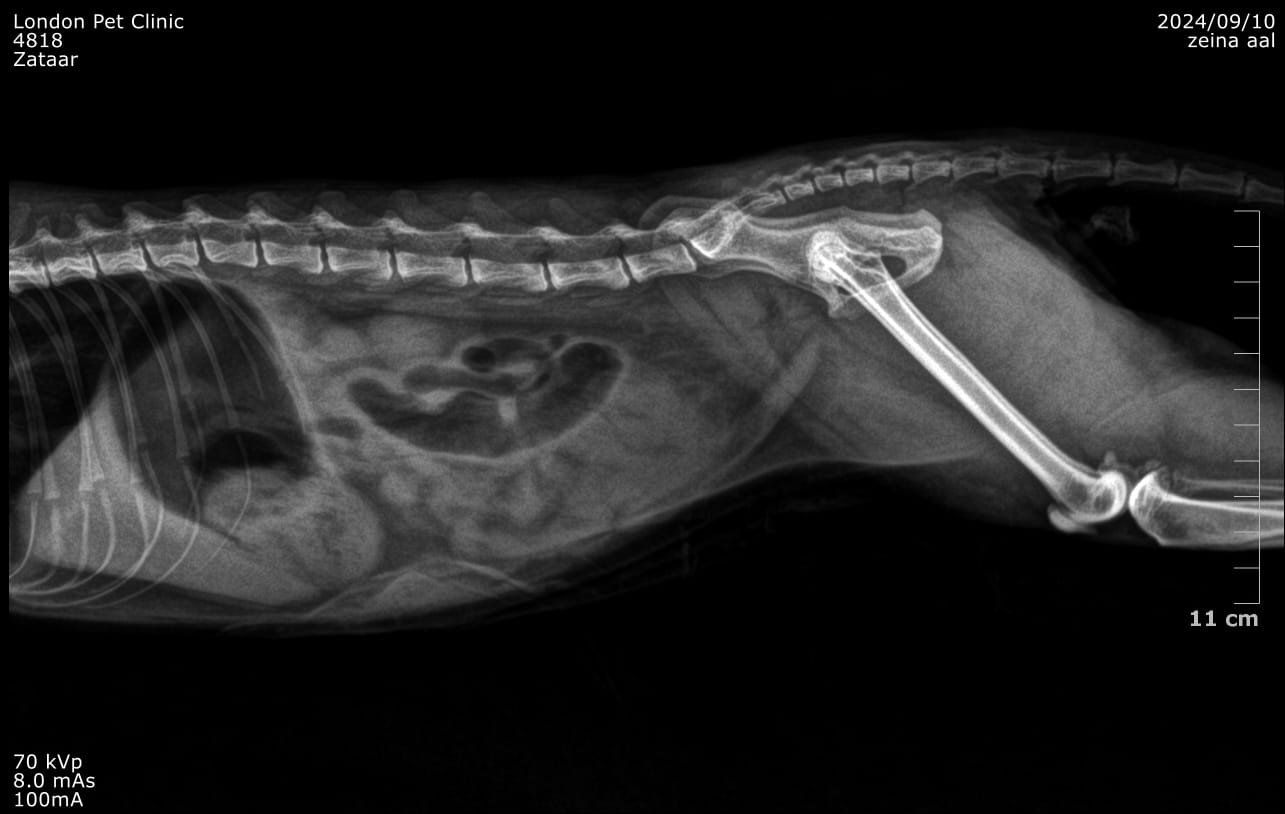

Abdominal radiographs: May show a gas--distended stomach with clogging clump

Abdominal ultrasound: was consistent of GOO due to hairball with fluid accumulation in the stomach

Trichobezoar causing chronic GIT signs in a 5 years old cat and lately more aggressive presentation

Large hairball lodged in the pyloric antrum

Post-Operative X ray